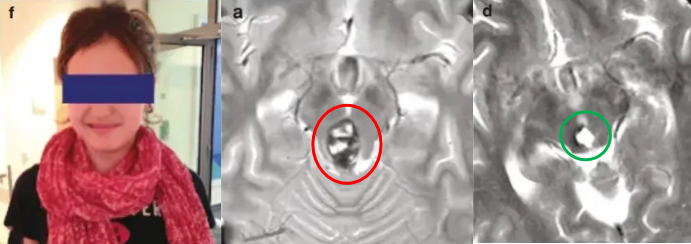

手术正式开始,这是一场与死神的争夺赛,而结果却出乎所有人意料——手术全切脑海绵状血管瘤,喜喜术后无任何并发症,顺利出院后她笑容如初!

2个月时间内,喜喜的癫痫发作越来越频繁,症状也更加严重,甚至在一次夜间被救护车紧急送医。一检查才发现,喜喜的脑子里有大瘤子!肉眼可见的占位位于大脑深处的松果体区,并已经出现了梗塞性脑积水。

面对喜喜此时的情况,当务之急是缓解脑积水症状。于是,巴教授立即进行了内镜下第三脑室造痿术,术后喜喜无任何并发症,也没有再出现癫痫发作。

于是没过不久,巴教授再次为喜喜主刀手术。巴教授选择经幕下小脑上入路暴露病变,术中发现病变为典型的海绵状血管瘤,而且还出现了新鲜的病灶内出血,很难想象如果没有及时手术,喜喜又将面临怎样的危急时刻。

所幸,手术最终成功全切脑海绵状血管瘤,术后喜喜的恢复情况令人欣慰,没有出现任何术后并发症,在乐观的家庭氛围感染下,当初那个爱笑的女孩又回来了!